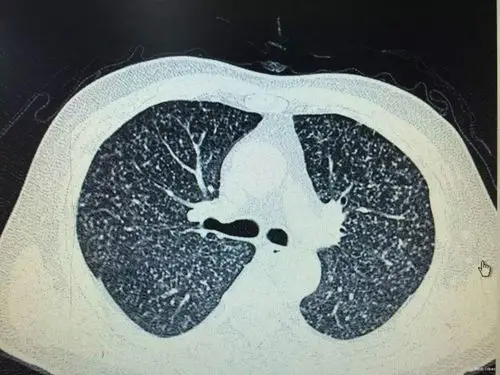

双肺弥漫性病变_肺结核

粟粒型肺结核